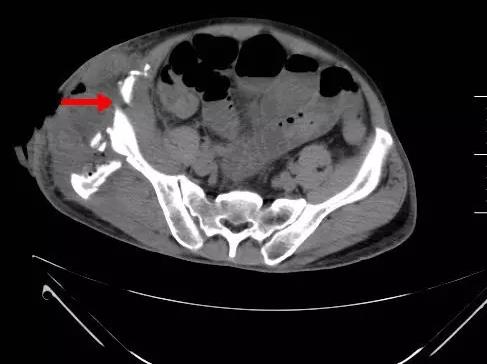

小肠疝出右侧腹壁皮下,合并肠梗阻

右侧骨盆粉碎性骨折